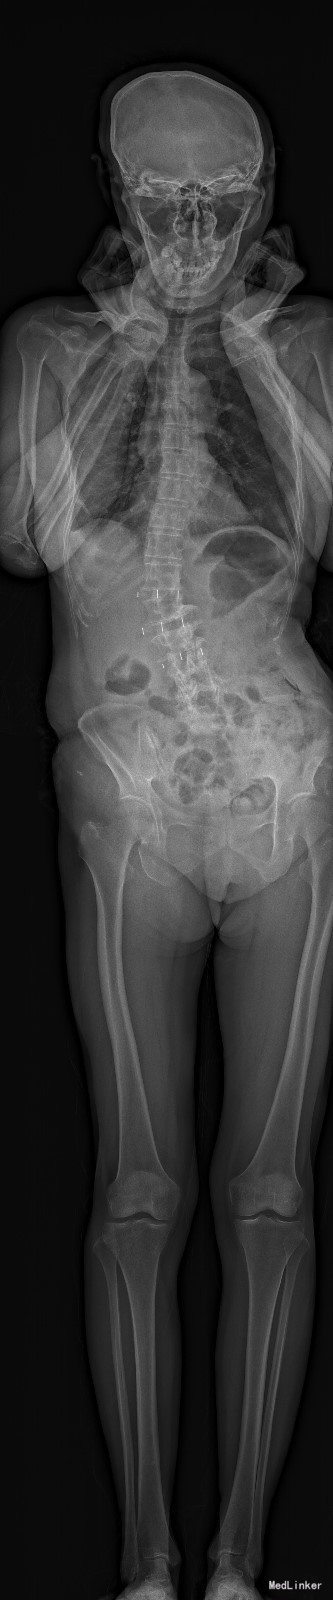

主诉:右下肢麻木11年,腰部酸痛无力 现病史:女性患者,65岁,患者于11年前无明显诱因下出现右下肢麻木,自大腿至右踝部,站立位加重。未予重视,后期出现腰臀部僵硬,弓背僵硬无力,自主行走距离不足200米,曾于06年经X线平片及MRI检查:腰椎椎管狭窄伴有腰椎滑脱,椎间盘突出等。

查体:侧弯畸形,右臀部及右下肢麻木疼痛,腰部活动受限,难以站立。右侧支腿抬高试验60°。双下肢肌力肌张力可。 辅助检查:平片:腰椎侧弯,椎体滑脱,曲度后凸 磁共振:L2-3,L4-5,L5-S1腰椎椎管狭窄,l2-3L3-4L4-5L5-S1腰椎间盘突出,腰椎退变

诊断: 腰椎侧弯,腰椎间盘突出 治疗:1期微创侧路椎体融合术+2期 微创后路经皮内固定术

随访:患者戴支具术后可早期下床活动,术后三周后行后路固定手术